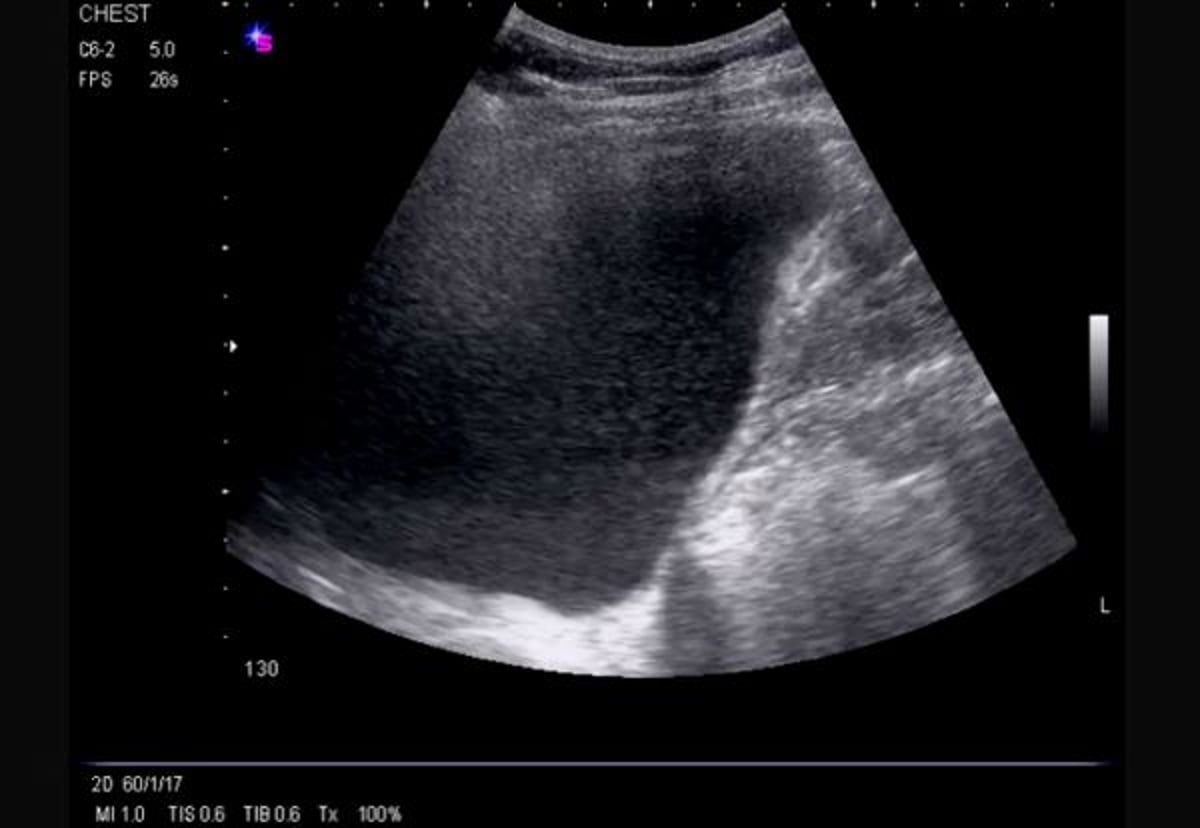

Латеральное УЗИ грудной клетки (справа)

На этом УЗИ виден масивный ничем не ограниченный выпот справа, вызывающий инверсию половины диафрагмы и демонстрирующий эхогенность.

Image courtesy of Najib M. Rahman, BMBCh MA (oxon) DPhil.